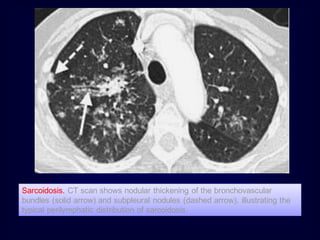

Rule no. 3

A middle or upper lung predominant distribution

suggests: (Mycobacterium Settle Superiorly in

Lung)

1. Mycobacterial or fungal disease

2. Silicosis

3. Sarcoidosis

4. Langerhans Cell Histiocytosis

Sarcoidosis. CT scan shows nodular thickening of the bronchovascular

bundles (solid arrow) and subpleural nodules (dashed arrow), illustrating the

typical perilymphatic distribution of sarcoidosis.

• 193.

Sarcoidosis. CT scanshows nodular thickening of the bronchovascular bundles (solid arrow) and subpleural nodules (dashed arrow), illustrating the typical perilymphatic distribution of sarcoidosis.